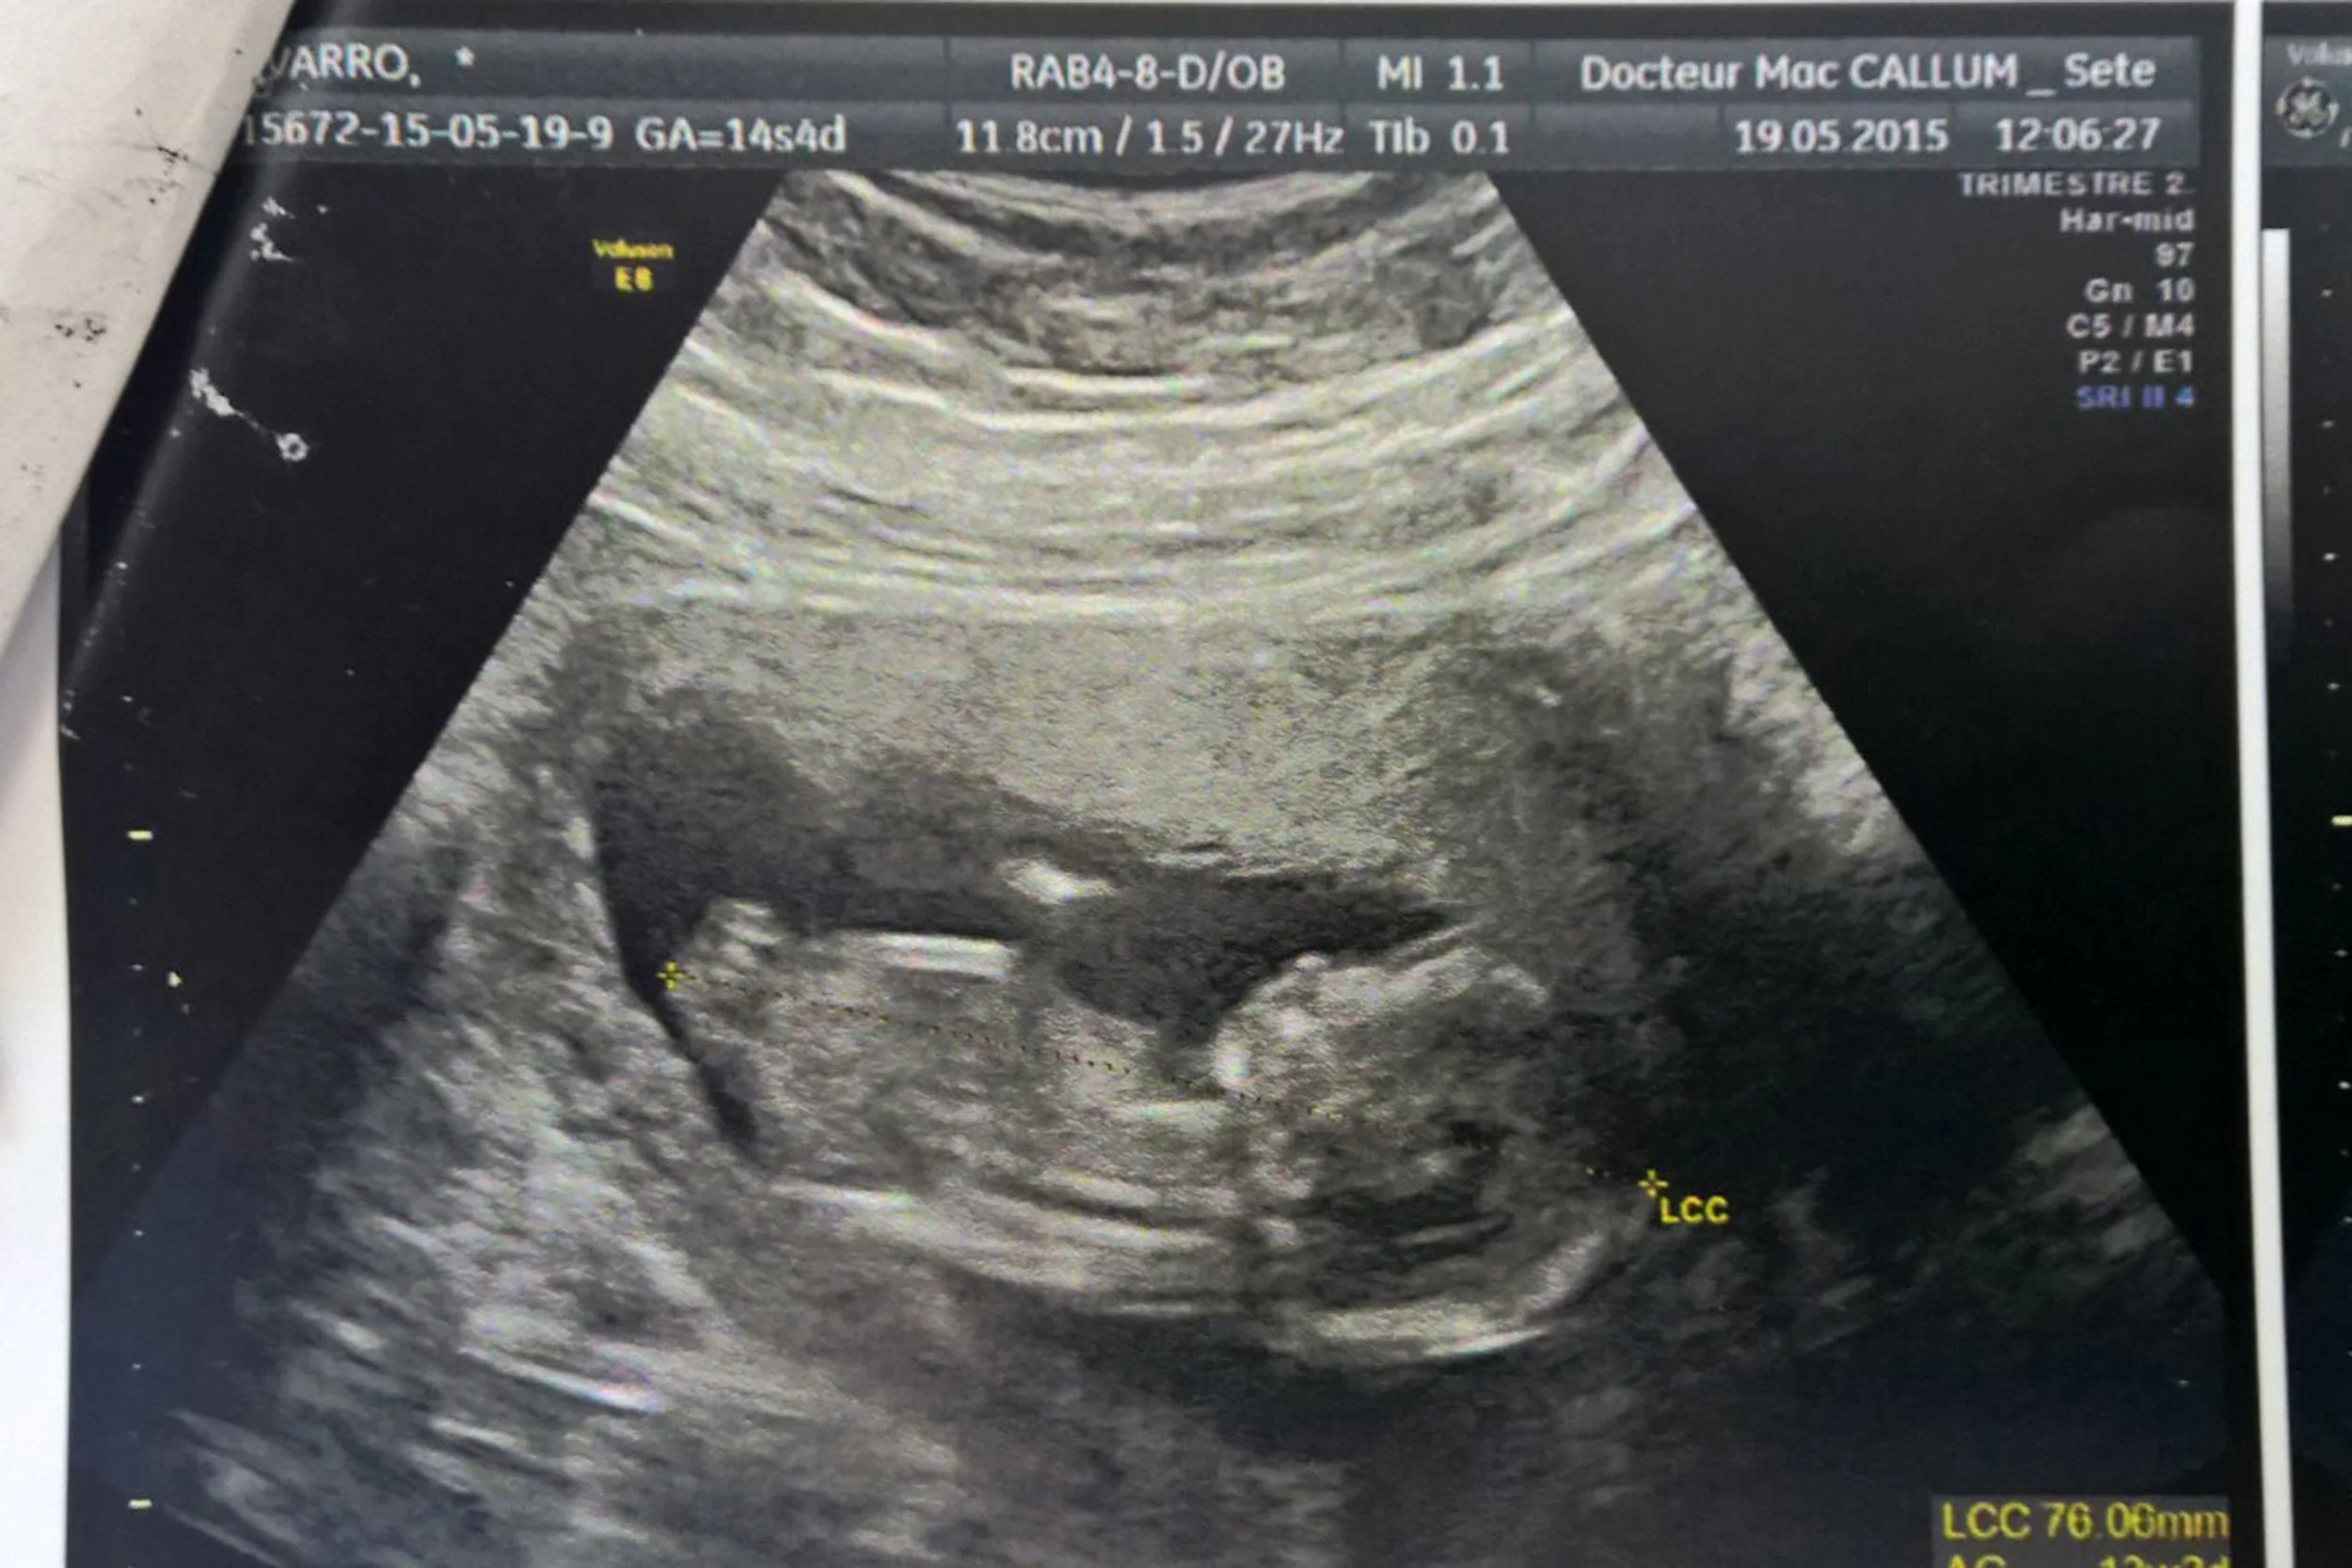

I have not yet deeply, truely realized, while I have been three months and a half pregnant. I think that, since I can't feel him/her move, everything remains abstract to me. I need FACTS. I have been extremely tired and kind of depressed (you know that feeling that, everything you do, you think you do crap.--> ME!), I haven't been sick, or nauseous. I lost 3 kilos though, don't have lots of appetite but my doctor says everything is under control and pretty good for both of us.